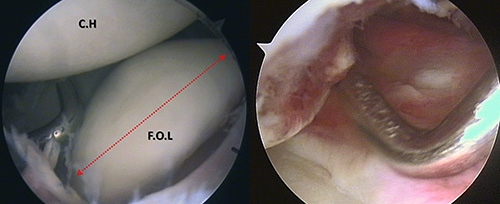

En posición de decúbito lateral, bajo anestesia general con bloqueo interescalénico, se realizó el examen artroscópico, con el cual se evidenció una fractura osteocondral de la región anterior de la cabeza humeral con un fragmento articular libre, de aproximadamente 2 cm x 2 cm (Fig. 6A), para lo cual se determinó que la reparación anatómica del mismo, solo podría realizarse mediante un abordaje mínimo por anterior. En asociación a dicha lesión, se observó una lesión de Bankart posterior (Fig. 6B) la cual fue prioritariamente reparada con la reinserción capsulo-labral posterior mediante el uso de suturas y un anclaje óseo (Fastak®, Arthrex®, Naples, Florida, USA), obteniendo una reducción anatómica del labrum.

Figura 6A: Visión por portal antero-lateral: Fragmento libre Osteo-condral mantenido por gancho explorados por portal posterior, demarcación del defecto óseo de la cabeza humeral.

Figura 6B: Visión por portal antero-lateral: Lesión de Bankart Reversa la cabeza humeral.